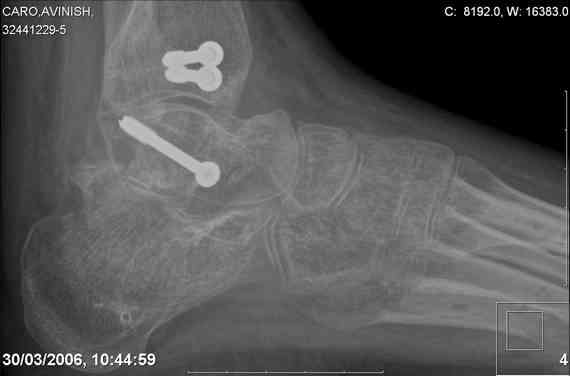

ya by popytalsya sobrat talus anatomichno,seichas pozdno operirovat iz za oteka,po etomy distrakziya apparatom budet optmalna.Posyalu vam podobyai moi sluchai.

14 years old girl

Fall from height ( 3rd floor)

Compressed fractures of L1-L2

Fx of orbital bone

Mark, судя по снимкам в день поступления произведен А.В.Ф., а остеосинтез ч-з какое время произведен?, остеосинтез произвели открытым способом?( на снимке п/о рубцы).

aparat postavlen v den postupleniya,rastaynuli, vpravili zakryto naskolko vozmoghno, a kogda otek spal sdelali otkrytoe vpravlenie.Teryat tut nechego, moghno tolko uluchshit.